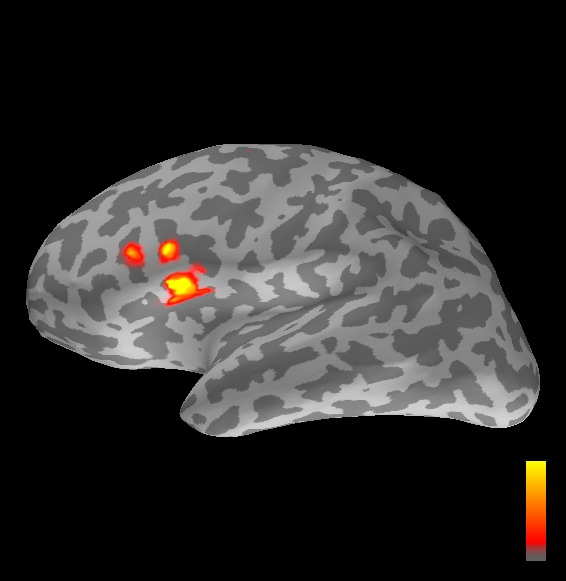

5.2 Results

We applied the ASMC sampler to MEG topographies taken from the above recordings by selecting specific time points according to the previous analysis; the parameter values in the algorithm were the same as those used for the analysis of synthetic data, with the only exception of the noise standard deviation , here estimated from the pre–stimulus interval. In order to validate the results of the ASMC, we also computed source estimates using three other methods: a PF, that approximates the posterior distribution for the current dipoles conditioned on the data up to the selected time point; dSPM, which is based on a distributed source model with an –prior, and consists in normalizing the Tikhonov regularized solution by the noise standard deviation; and sLORETA, which is similar to dSPM but is claimed to have a smaller localization bias. Figure 4 shows the results at , and ms after the stimulus onset. The results are visualized on a computer representation of the brain obtained by “inflating” the cortical surface: gray levels contain the anatomical information, light gray representing gyri and dark gray representing sulci; the activity estimate is coded in color scale, increasing from red to yellow. Importantly, this visualization allows activity in the sulci to be clearly visible; on the other hand, since neighbouring volumes may be moved apart by the inflation process, distinct activity regions are often due to underlying volumetric masses that are very close to each other.

Before describing the results, let us comment on the qualitative difference between the images produced by the ASMC sampler and the PF, on the one hand, and those produced by dSPM and sLORETA, on the other. First of all, we point out that all the quantities shown in the images of Fig. 4 are somehow related to the probability of activation at specific locations. Indeed, for both the ASMC and the PF we plot the approximation of the intensity measure (3.8); for any single grid point, this value can be interpreted as the probability of a dipole being at that location, while it integrates, over a given volume , to the mean number of dipoles within . As for dSPM, the represented quantity is a statistical value that is –distributed under the null–hypothesis of zero activity; as a direct consequence, it also yields a probability of activation, which is however not constrained to be dipolar. Similar considerations apply to sLORETA, although with a different statistical distribution. Importantly, the representation of the results is clearly affected by the setting of the visualization threshold. Owing to the explained differences between the methods, it seems reasonable to use a different value for each method. At the same time, since the plotted quantity is a probability of activation, it seems right to use the same thresholding for different time points. In this connection, the thresholds in Fig. 4 have been chosen by hand following the guidelines just outlined.

Using the same thresholding and parameters at different time points makes the four methods respond differently to the diverse intensities of the different sources. Whenever a stronger source is active, both sLORETA and dSPM will tend to produce widespread estimates, while weaker sources will be represented as small active areas. The behaviour of the ASMC and of the PF is the opposite: a stronger signal will lead to a precise localization of a dipolar source, and then to a focal marginal distribution for the location; a weaker signal will translate to higher uncertainty on the source position, and therefore a more widespread posterior map.

At ms, the ASMC localizes again two sources: a stronger one in the right primary somatosensory cortex, and a weaker one in the left posterior frontal area. Both of them seem to be compatible, for timing and location, with the results in Mauguiere et al. (1997), the left dipole corresponding to the Frontal Ipsi source. Once again, the other three methods only recover the stronger source.